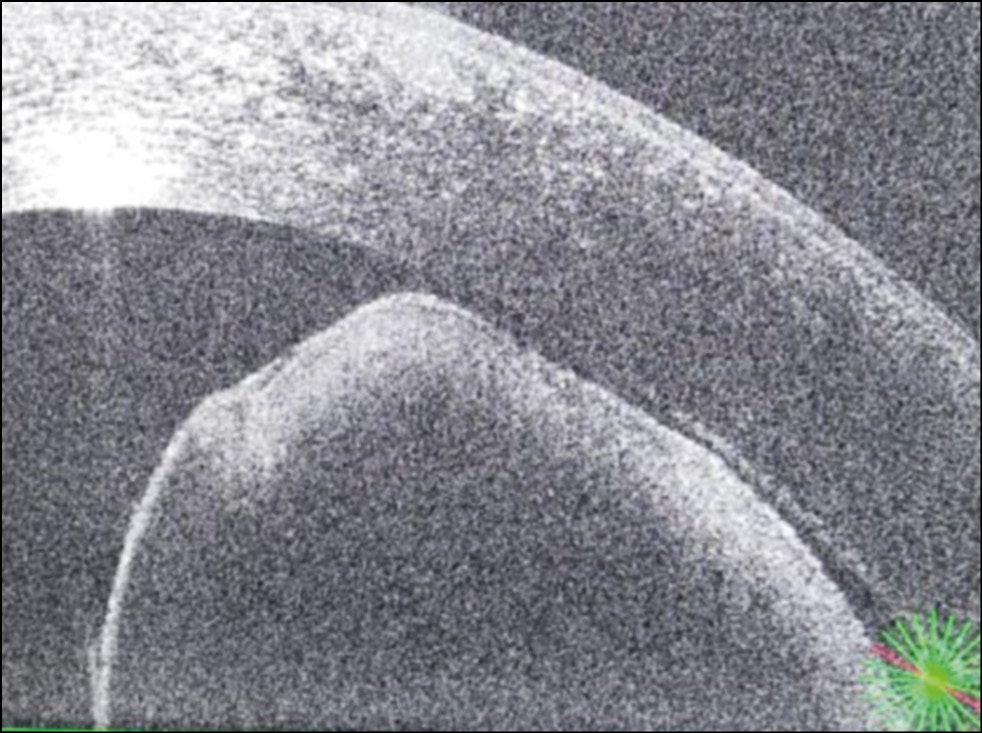

По данным оптической когерентной томографии у пациента имеется овальное кистовидное образование, исходящее из тканей радужки с гиперрефлективной капсулой и гипорефлективным содержимым (рис. 3).

Рис. 3. Оптическая когерентная томография радужки OS. Кистовидное образование с гиперрефлективной капсулой и гипорефлективным содержимым.

Гистологическая картина соответствовала диагнозу «киста пигментного эпителия радужки». На контрольном осмотре в июне 2021 г. отмечен благоприятный анатомический и функциональный результат.